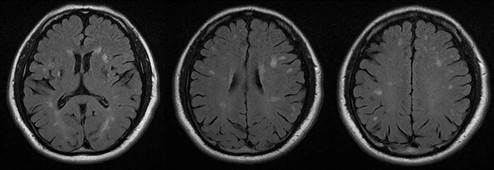

Figura 2 RM T2-FLAIR Axial. Lesiones hiperintensas multiples en sustancias blanca subcortical y sustancia gris profunda bilateral